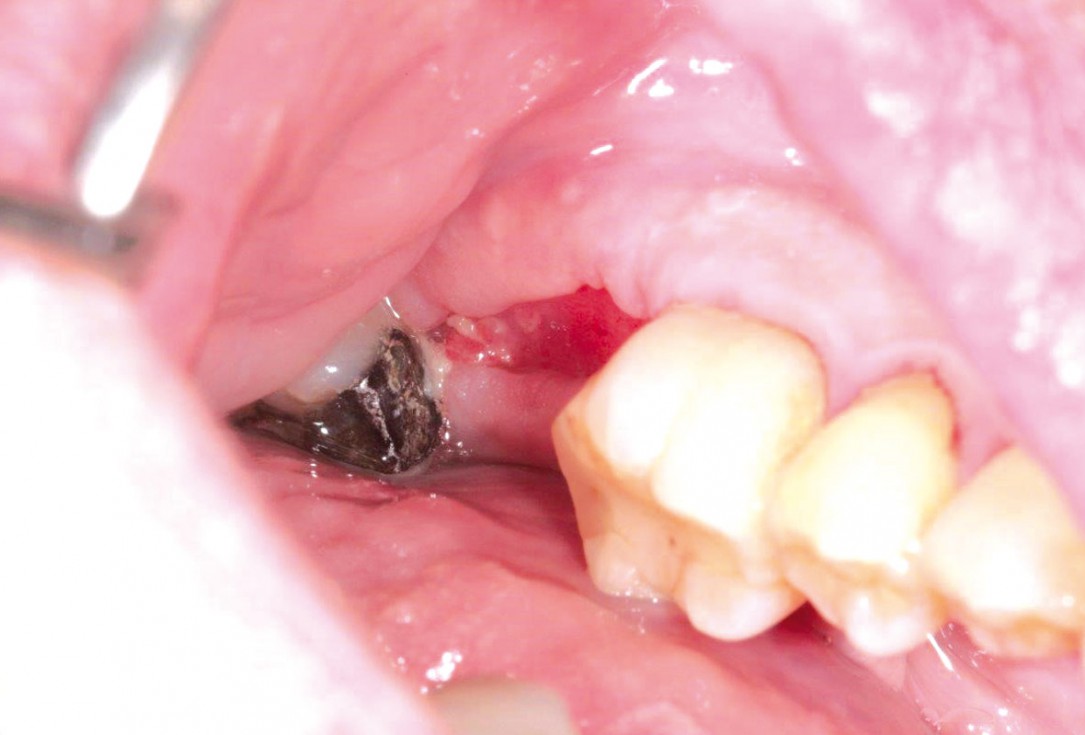

Clinical situation before extraction and implantation